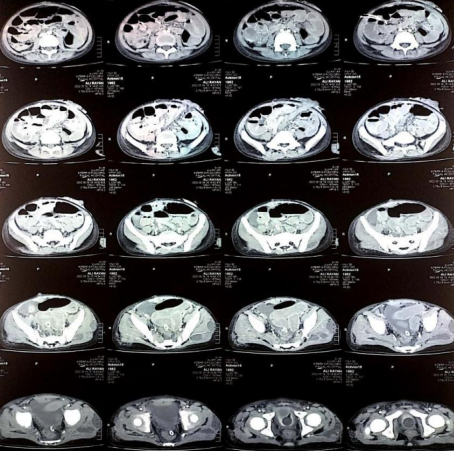

After stabilization his endoscopy was performed which showed a bleeding dieulafoy lesion in the 1st part of the duodenum, clotted blood in the stomach and attenuated blood in the 2nd and 3rd part of duodenum. Hemoclips were applied at the site of lesion and hemostasis secured. (Fig. 2) After hemoclipping his melena stopped and his hemoglobin level was maintained. He was on our follow up in paediatric gastroenterology clinic and his repeat endoscopy after 2 months showed hemoclips in place and no active bleeding. (Fig. 3) His Hemoglobin was 12.5g/dl on follow up and he is thriving well.

Figure 1, 2, 3

Figure 3